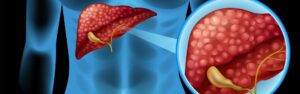

L’essentiel à retenir : Pendant la ménopause, le foie peine à éliminer les déséquilibres ... Lire plus